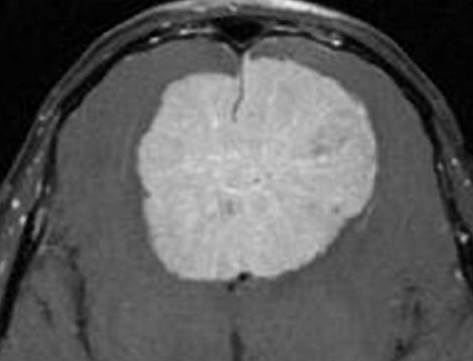

Meningiomas that extend into the superior sagittal sinus on at least one wall are known as parasagittal meningiomas.

There is a strong connection between the superior sagittal sinus and these types of tumors. This sinus is a huge venous canal that is situated in the middle of the two hemispheres of the brain. It receives the majority of the blood that is drained from the brain through the veins. Parasagittal meningiomas can invade this superior sagittal sinus partly or completely.

Parasagittal meningiomas have the potential to become enormously large and exert continuous stress on the underlying structure, which can result in brain swelling or edema. A tumor can occasionally penetrate the overlaying cranial bone, causing a bump to be felt beneath the scalp. Parasagittal meningiomas can arise anywhere along the superior sagittal sinus, including the frontal, parietal, and occipital lobes.